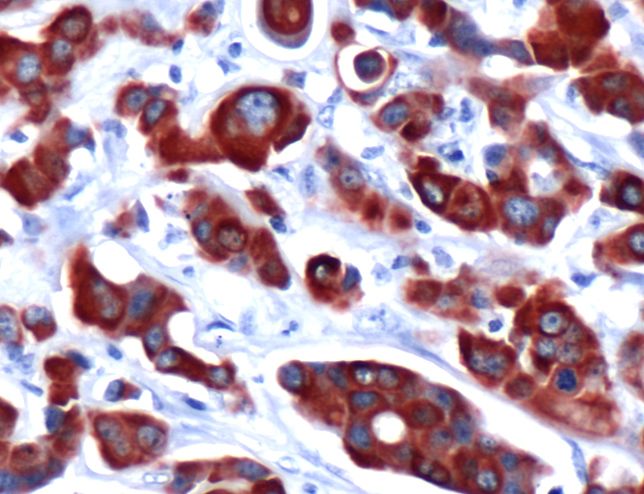

Keratin 7 (SP52)

Cytokeratin 7 is a basic cytokeratin which is found in most glandular and transitional epithelia but not in the stratified squamous epithelia. Keratin 7 is expressed in the epithelial cells of ovary, lung, and breast but not of colon, prostate, or gastrointestinal tract.